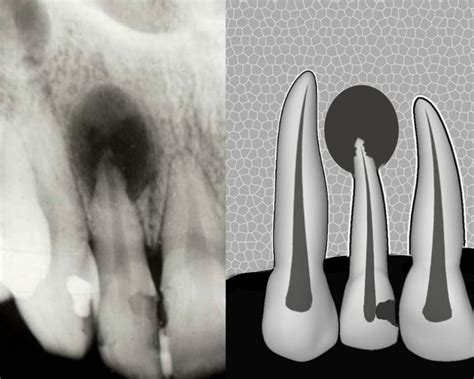

Quiste Radicular

Es el quiste odontogénico más frecuente. Puede situarse en el ápide radicular, lateralmente a la raíz de los dientes o quedarse en el tejido óseo tras la extracción dentaria sin ser descubierto.

Las técnicas radiográficas son esenciales para la evaluación diagnóstica. La radiografía periapical intraoral permite visualizar detalles de lesiones alrededor del ápice dental, mientras que la radiografía panorámica ofrece una visión general de ambos maxilares, útil para identificar lesiones quísticas extensas o múltiples.